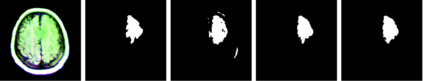

Medical imaging plays a crucial role in modern healthcare by providing non-invasive visualisation of internal structures and abnormalities, enabling early disease detection, accurate diagnosis, and treatment planning. This study aims to explore the application of deep learning models, particularly focusing on the UNet architecture and its variants, in medical image segmentation. We seek to evaluate the performance of these models across various challenging medical image segmentation tasks, addressing issues such as image normalization, resizing, architecture choices, loss function design, and hyperparameter tuning. The findings reveal that the standard UNet, when extended with a deep network layer, is a proficient medical image segmentation model, while the Res-UNet and Attention Res-UNet architectures demonstrate smoother convergence and superior performance, particularly when handling fine image details. The study also addresses the challenge of high class imbalance through careful preprocessing and loss function definitions. We anticipate that the results of this study will provide useful insights for researchers seeking to apply these models to new medical imaging problems and offer guidance and best practices for their implementation.